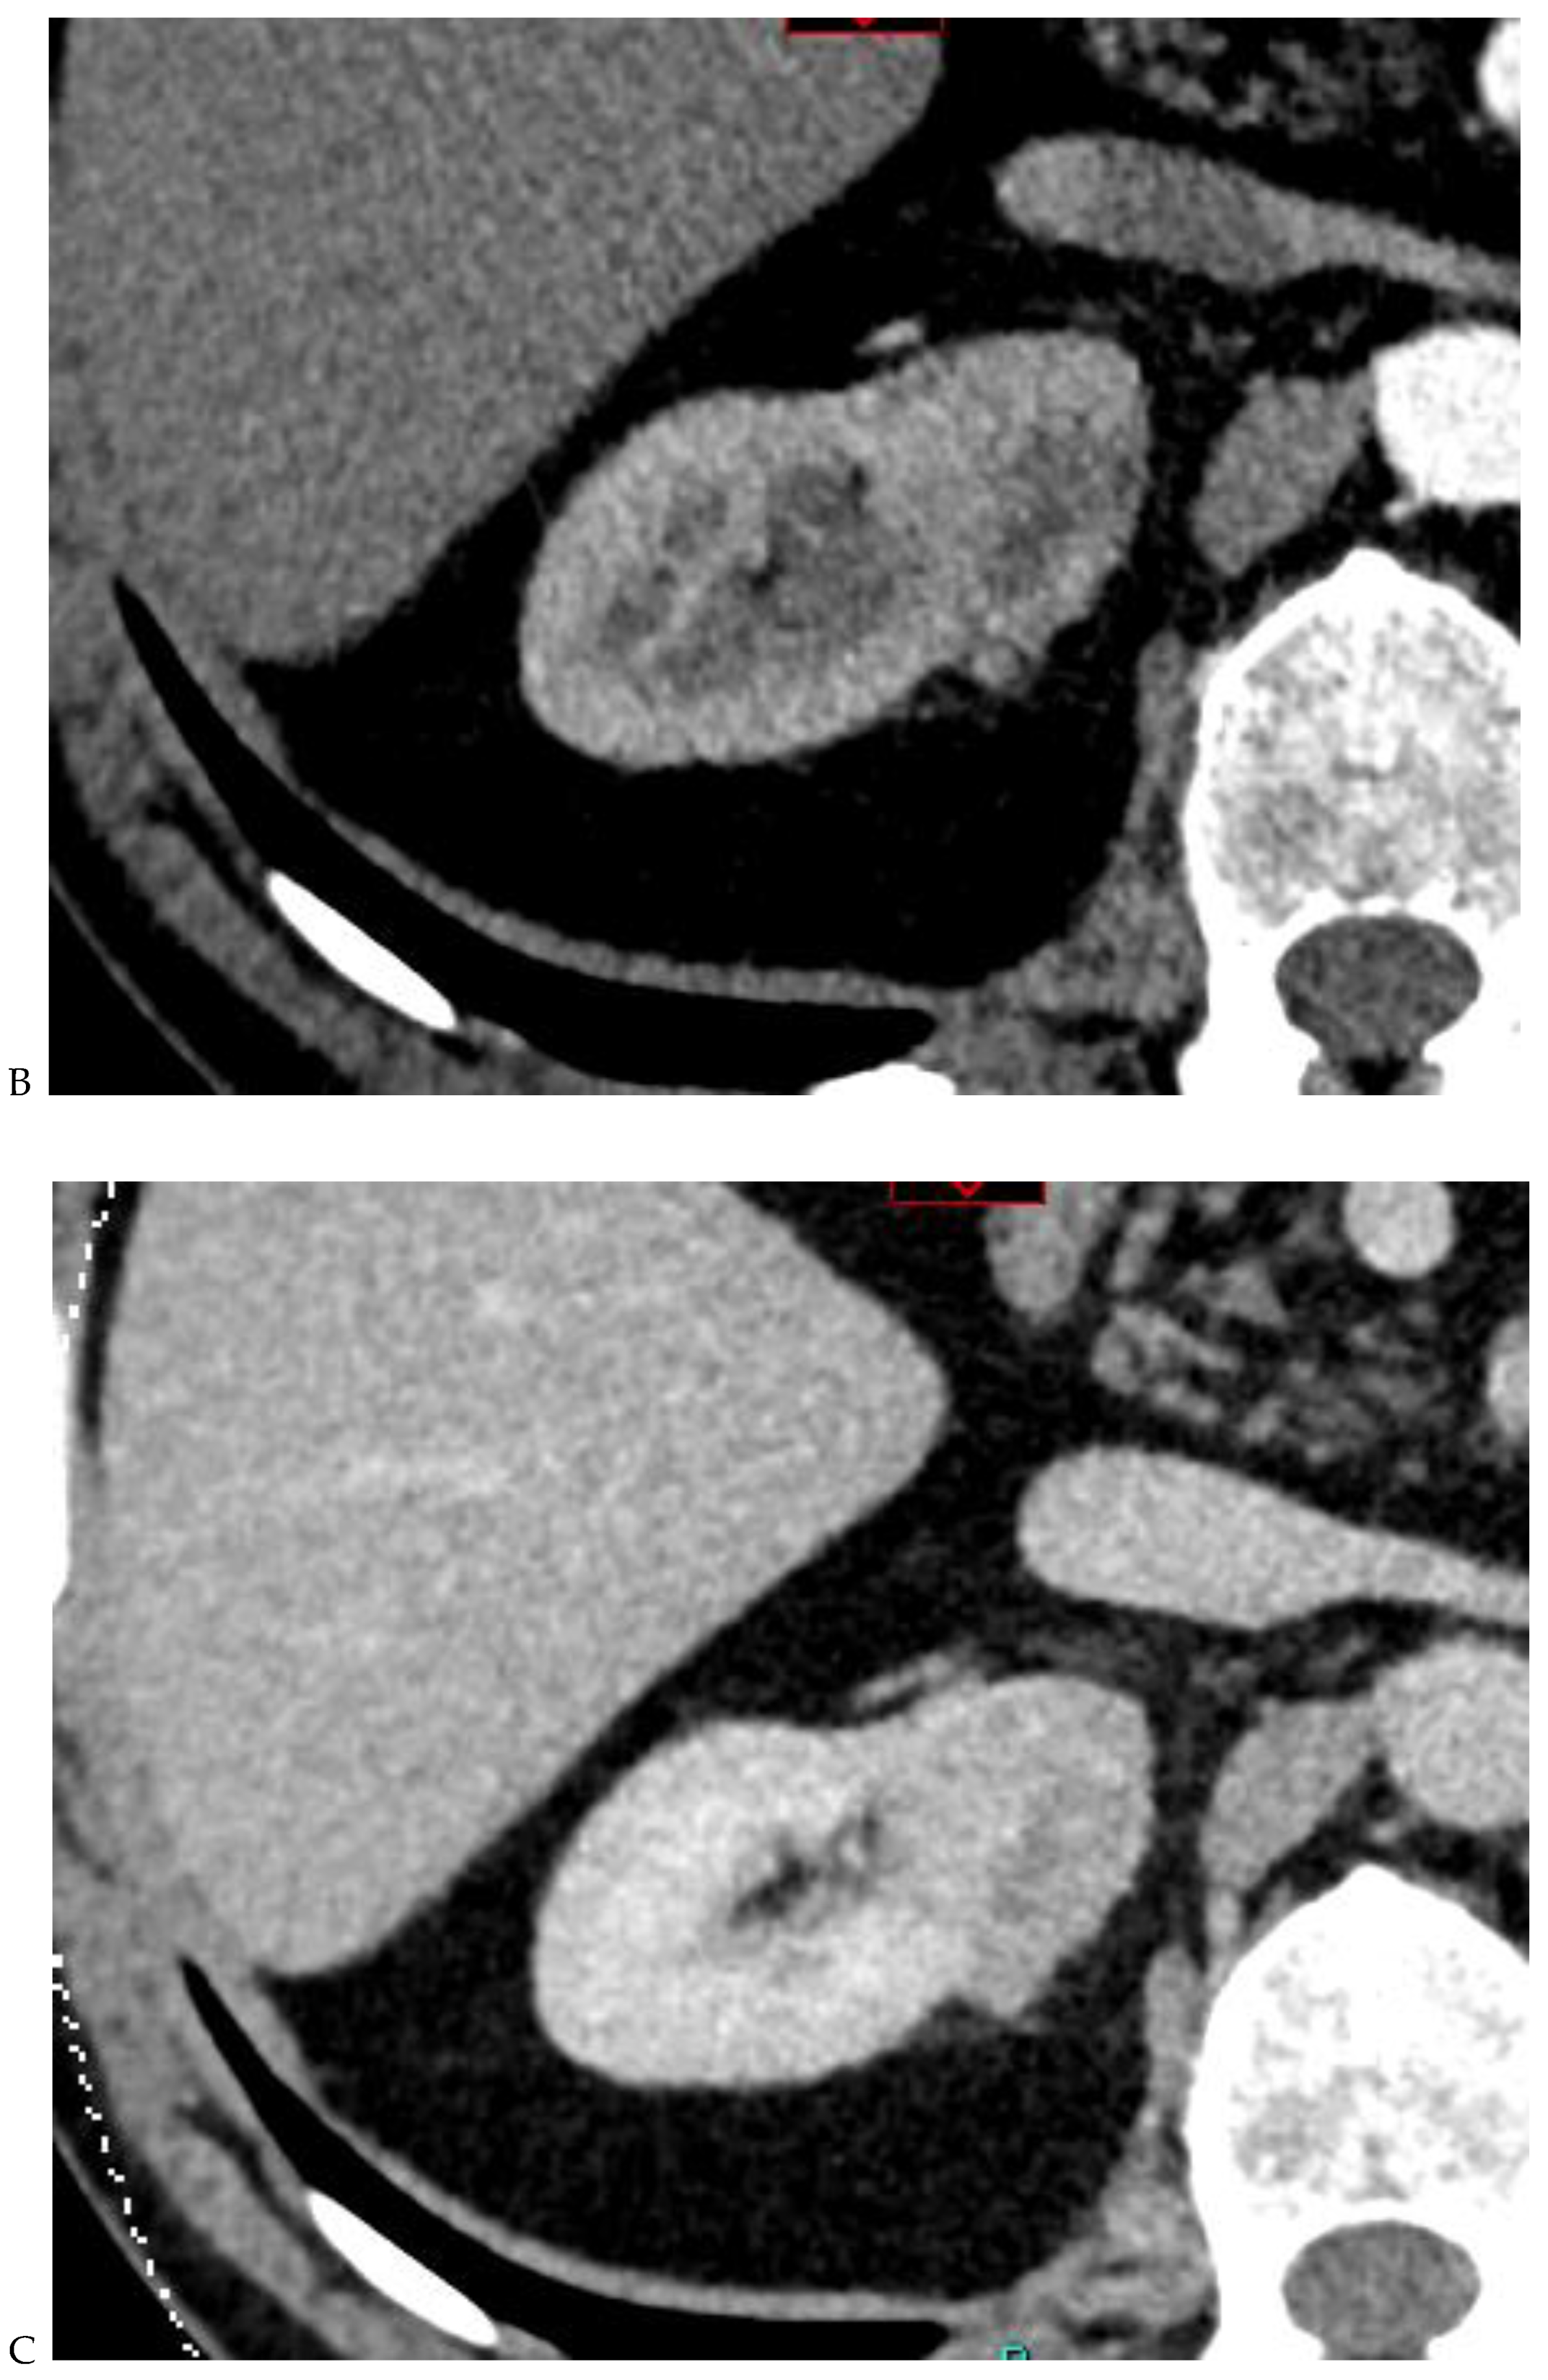

Figure 3.

CT aspect of a chromophobe renal cell carcinoma in the left kidney of a 68-year-old-woman. (A) Unenhanced image. Presence of an isodense, homogeneous solid lesion at the medium part of the left kidney. (B) It appears moderately hypervascularized on the corticomedullary phase image, with hyperdense septa. (C) There is progressive washout on the nephrographic phase image and the lesions appears hypodense relative to the renal parenchyma (C). (D) Macroscopic view of the lesion after partial nephrectomy. Courtesy of Pr S. Ferlicot, Department of Pathology, Bicêtre Hospital.